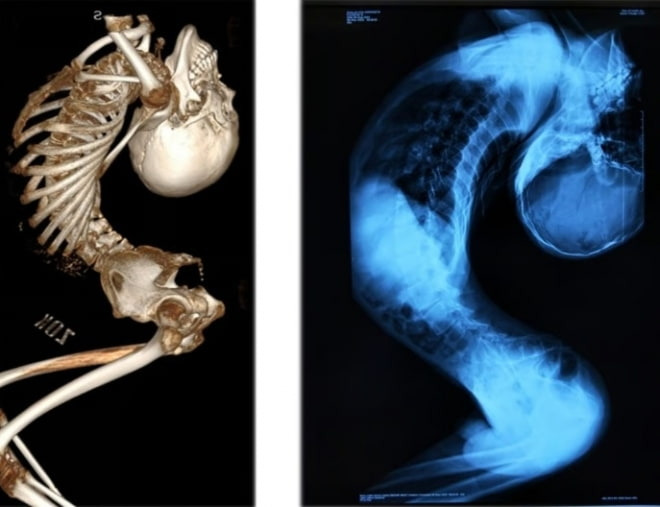

대수술 후, 폴더 소년은 긴 회복 과정을 거쳐야 했습니다. 수술은 성공적이었지만, 회복 과정은 쉽지 않았습니다. 그는 재활 치료를 통해 다시 걷는 법을 배우고, 일상생활로 돌아가기 위해 많은 노력을 기울였습니다. 그의 의지와 가족의 지원이 큰 힘이 되었습니다.